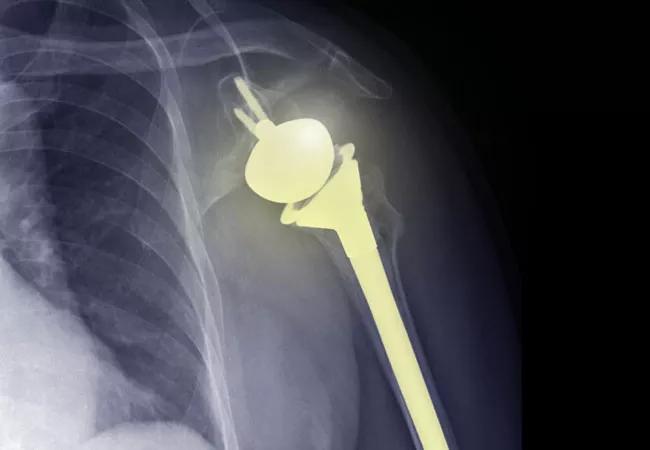

Identifying the Patient, Disease, Surgical and Implant Positional Factors that Predict Outcomes Following Total Shoulder Arthroplasty

Total shoulder arthroplasty

The number of shoulder arthroplasty procedures performed in the United States continues to rise, with current estimates ranging from 55,000 to 80,000 per year and increases of 300% or more expected in the coming years. While total shoulder arthroplasty (TSA) is the preferred surgical treatment for advanced glenohumeral arthritis, a subset of patients do not experience clinical improvement or sustain a complication. Glenoid component loosening is reported as the most common long-term complication of anatomic TSA and a common reason for revision surgery.

In addition, the factors associated with poor short- and long-term clinical outcomes after anatomic TSA are still not well understood, in part due to the lack of large prospective cohort studies allowing for multivariable analysis. Furthermore, while an association between glenoid component loosening on plain radiographs and worse clinical outcomes, including the need for revision surgery, has been shown at longer follow-up, the significance of early radiographic changes on longer-term clinical outcome has not been established, nor have the factors associated with glenoid component loosening been well-defined. The ability to reliably and accurately measure subtle radiographic factors longitudinally following anatomic TSA may allow for a deeper understanding of the relationship between short- and longer-term clinical outcomes.